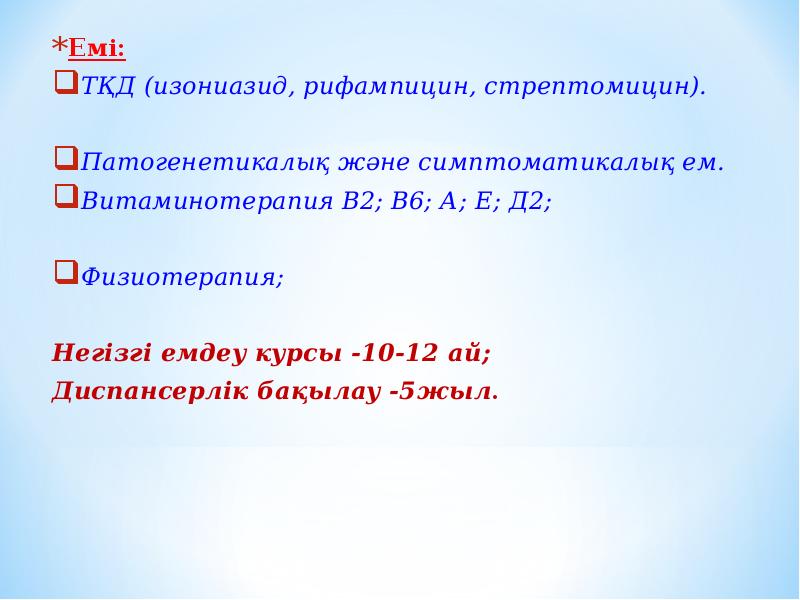

Лечение туберкулеза: Методики химиотерапии

Раздел: Визуальный дайджест